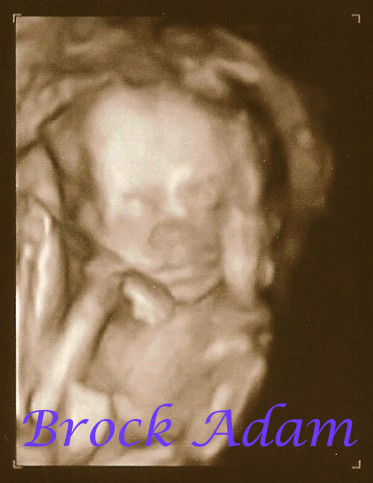

Baby A is a BOY!! I think I grinned for 10 minutes!  Heart rate 152.  Measuring exactly 22 weeks. ~1 lb.  Brock Adam--meaning--Braxton comes from Brock's town....so we like that they both were in each other's meanings.  Adam--sticking to Bible middle names.